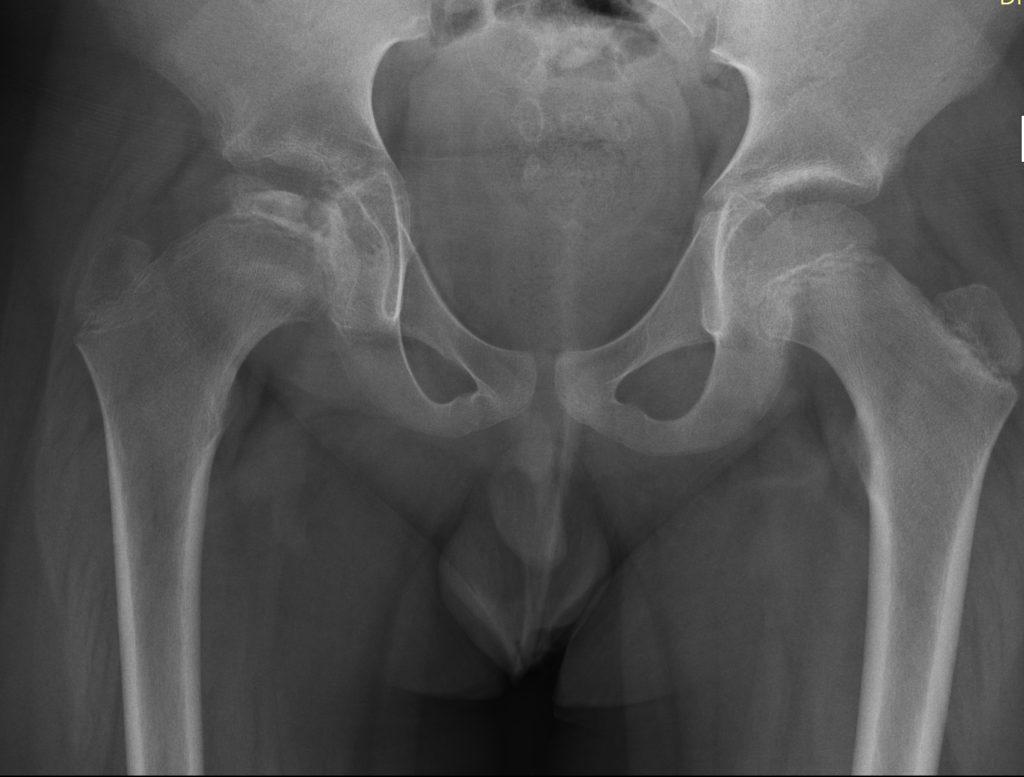

В основе диагностики болезни Легга-Пертеса лежит рентгенологическое исследование сустава, с его помощью специалисты определяют стадию и степень деформации. Согласно полученным результатам врач выбирает оптимальные способы лечения. Дополнительными диагностическими методами служат:

Рентгенологическое обследование

При подозрении на болезнь Пертеса делают не только снимки в стандартных проекциях, но и рентгенограмму в проекции Лауэнштейна. На основании полученных результатов исследования врач ставит диагноз, чаще всего используя классификации Сальтера-Томсона и Кэттерола.

Ортопед, изучая рентгенограмму, выявляет особенности строения костей и степень деформации суставной головки.

Снимки позволяют увидеть метафизарные изменения, линию субхондрального перелома и другие патологии.